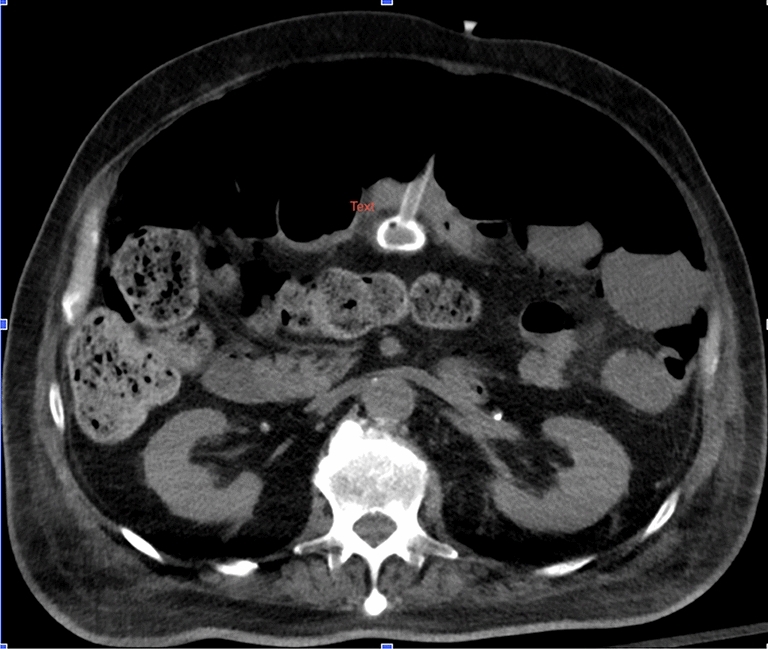

Outcomes of Multiple Approaches to Biosynthetic Mesh Incisional Hernia Repair after Kidney Transplant

Omar Bellorin, MD, FACS, FASBMS; Amy L Holmstrom, MD; Gregory Dakin, MD; Kofi Atiemo, MD; Dustin Carpenter, MD; Rebecca Craig-Schapiro, MD; Sandeep Kapur, MD; Cheguevara Afaneh, MD; Weill Cornell Medical Center

Background: Post-operative incisional hernias are a common occurrence in the transplant population. Hernia following kidney transplantation further complicates repair due to the location of the operative incision. The goal of this study was to compare recurrence rates between various operative approaches after biosynthetic mesh incisional hernia repair in patients after kidney transplant.

Methods: Using a prospectively maintained database, a retrospective review was performed for patients undergoing elective incisional hernia repair following kidney transplantation from January 2017 to June 2022. All patients were on a steroid-based immunosuppressive regimen at the time of hernia repair. A Gibson incision was performed at the index surgery for kidney transplantation. Hernia repairs were approached either open or robotic assisted via an intraperitoneal onlay mesh (IPOM) technique or a robotic transabdominal preperitoneal (RTAPP) mesh technique. Biosynthetic mesh was used in all cases. Patients who were actively smoking and hernia surgery in the setting of perforations were excluded.

Results: A total of 96 patients were included; 21 underwent an open approach, 18 had an IPOM, and 57 had an RTAPP. Average follow-up was 24 months (range 6–48 months). There were no significant differences in age, sex, BMI, co-morbidities (diabetes, smoking history), or hernia defect size (p > 0.05). The average time to incisional hernia repair following kidney transplant was 5 ± 2 months. The open approach took significantly longer than the other approaches (156 min vs. 131 min RTAPP, 109 min IPOM; p < 0.001). There were no significant differences in surgical site occurrences (infection, seroma, hematoma, wound dehiscence) or postoperative morbidity (p > 0.05). Recurrence rates were highest in the IPOM cohort at 12 months (6.7% vs. 0% open, 1.9% RTAPP) and at 24 months (13.8% vs. 5.95 open, 1.9% RTAPP).

Conclusion: Biosynthetic mesh incisional hernia repair following kidney transplantation has the lowest intermediate term recurrence rate with an RTAPP technique. Intraperitoneal onlay mesh is the least durable repair when compared to both the open approach and RTAPP. Longer follow-up is necessary to determine durability of repair by operative technique in the kidney transplant population.